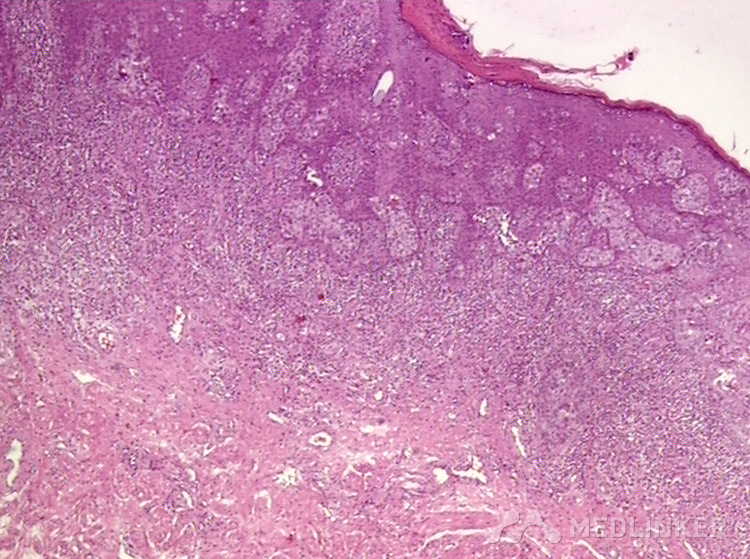

乳房外佩吉特病

后来我建议他做了活检,病理结果显示【乳房外Paget病】!

乳房外Paget病是一种什么样的疾病呢?原来它还有一个名字,就叫湿疹样癌,长的就是很像湿疹,但是按照湿疹怎么样也治不好!所以各位医生,如果觉得有自己治疗不好的顽固性湿疹,可能不是咱水平不行,是因为这个病不是湿疹,所以照着湿疹治疗效果肯定不好了。 另外如果得了阴囊湿疹持续超过半年一直不好的话,建议去医院皮肤科做病理活检。因为炎症和肿瘤的区别就是炎症是可以消退的,可以好一段时间再犯,而肿瘤是始终存在的,通过外用药膏是无法治疗好的。大家记住这个重要的鉴别点好了,【肿瘤是会持续存在的,药膏是治疗不好的】。 这个病的治疗并不困难,需要排除远处转移的肿瘤,发现了扩大切除,预后都会不错的。